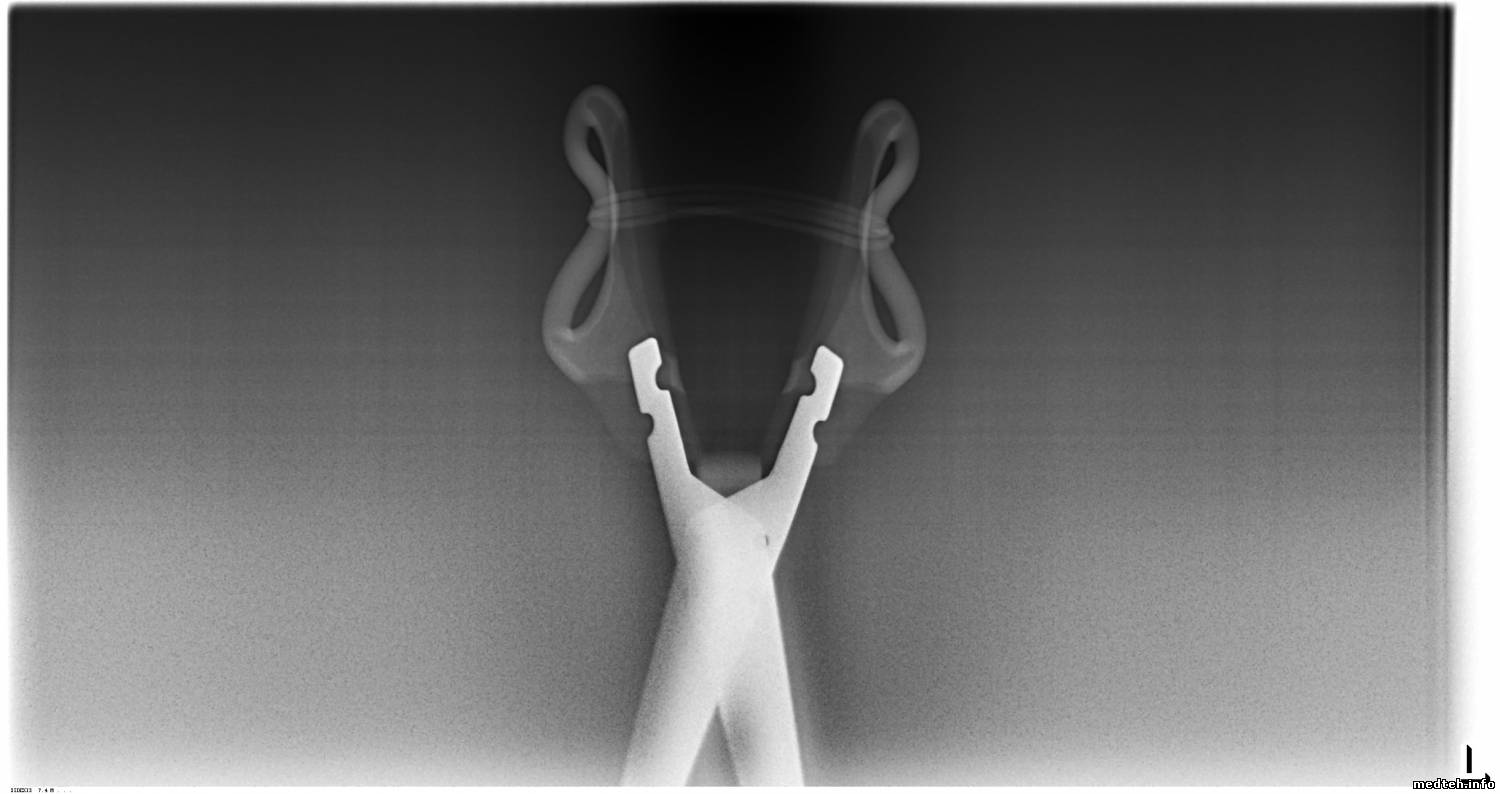

А что с ножницами сделали? shok

Подобное, с ним же. Вчера работал, сегодня - нет снимка. Аппарат не мой. Захожу, вижу копошится коллега. Нет снимка. Включение, тестирование (как будто) - готов. Снимаем - нет. shok

Стал осматривать - сдвинута приёмная часть, голубая кнопка запала. Давеча был электрик, делал вытяжку. Видать

Цитата ursa_majoris ()

похоже, приложился

. Короче, выключил, вставил - ноль! Отсоединил, включил - ему до лампочки - есть блок, нет блока. Никакой ошибки на дисплее. Вылечил так. Выключил комп, подсоединил, вкл панорамник. После загрузки вкл комп, активировал программу, потыкал табло панорамника, сделал снимок фантома (в комплекте) - работает! И так три раза для верности - работает!

Вопрос: эта штука - дура совсем тупая? Ей глаза выдрали, а она и не поняла? Не ожидал такого от SIRONы ireful rofl

7001323.jpg (71.4 Kb)